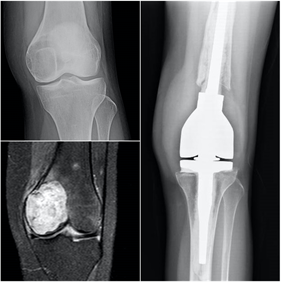

Tumor de células gigantes

El tumor de células gigantes es una lesión tumoral benigna pero localmente agresiva. Provoca lesiones líticas expansivas que se localizan fundamentalmente en las metáfisis y epífisis de huesos largos. La edad de aparición está entre los 20 y 50 años y se suele localizar con mayor frecuencia en la zona cercana a la rodilla, en la epífisis distal del fémur, en la tibia proximal y en el radio distal. Se describe la presencia de metástasis pulmonares en casi el 5% de los pacientes. Habitualmente el paciente refiere una historia de dolor persistente en torno a la rodilla, con afectación progresiva de la funcionalidad. Las fracturas patológicas suelen aparecer fundamentalmente en casos avanzados, con gran debilidad cortical. En la rodilla puede asociar derrame articular y fracturas osteocondrales por debilidad del hueso subcondral.